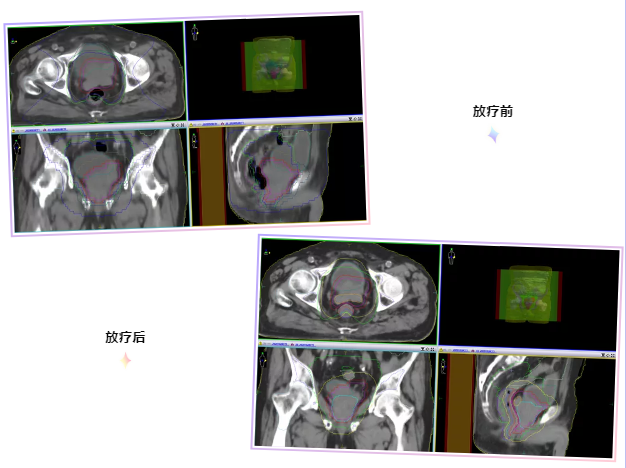

在放疗科医护人员的共同努力下,病人终于得到了有效治疗。很快奇迹就出现了,经一次治疗后,患者的严重血尿就有了明显改善。1周后就再也没有出现肉眼血尿。再次进行CT定位时,可见肿瘤也明显缩小了。